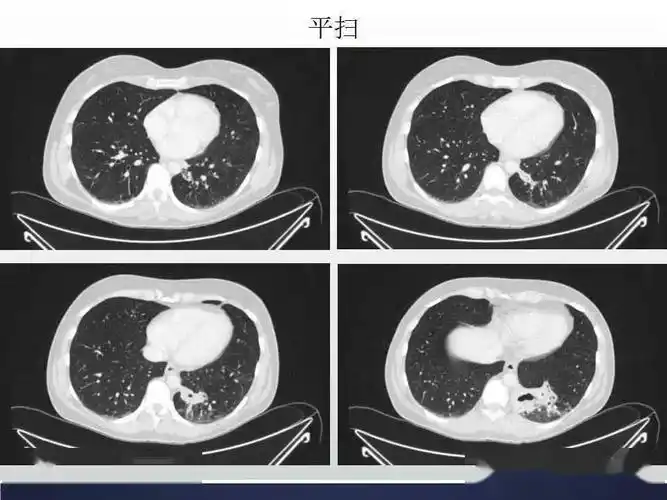

肺隔离症影像表现_郑孝飞